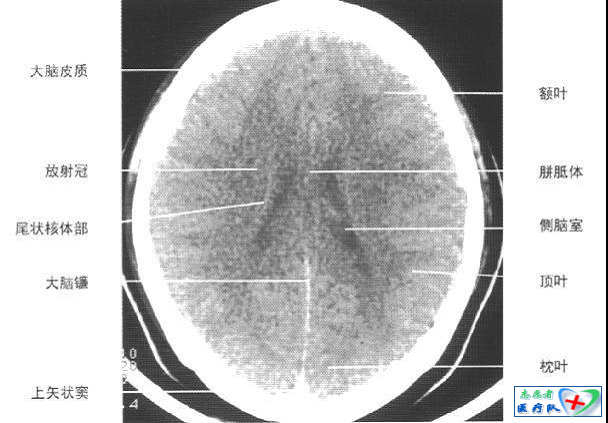

照片描述:大脑皮质下部层面